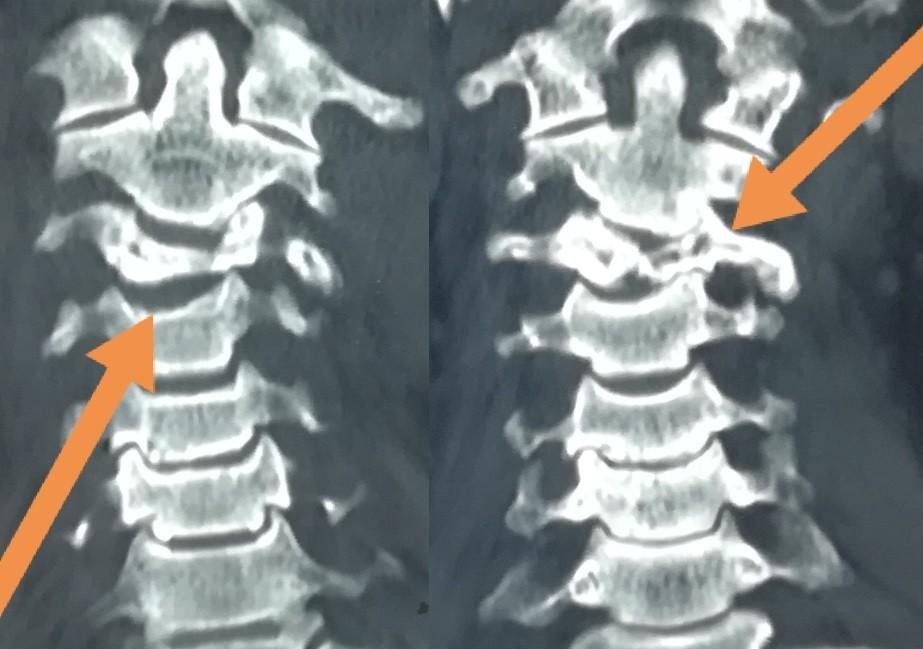

تثبيت امامي لكسر وتاكل بجسم الفقرة الثالثة العنقية

anterior fixation of a fracture and wear of the body of the third cervical vertebra

A successful anterior fixation surgery was performed to treat fracture and erosion in the vertebral body of cervical vertebrae. This specialized procedure aims to restore cervical spine stability and address vertebral damage resulting from injury or inflammation.

• Restoring cervical spine stability

• Relieving pressure on spinal nerves

• Preventing further vertebral damage